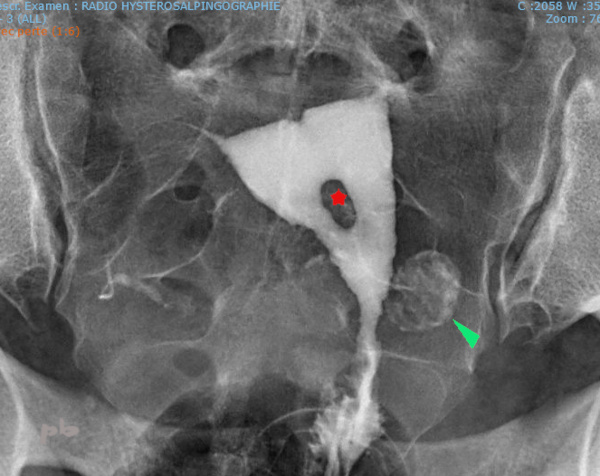

12 – Polypes multiples – Hystérosalpingographie (HSG)

Bilan réalisé dans le cadre d’une infertilité.

Multiples images lacunaires (►), de contours réguliers, moulées par le produit de contraste.